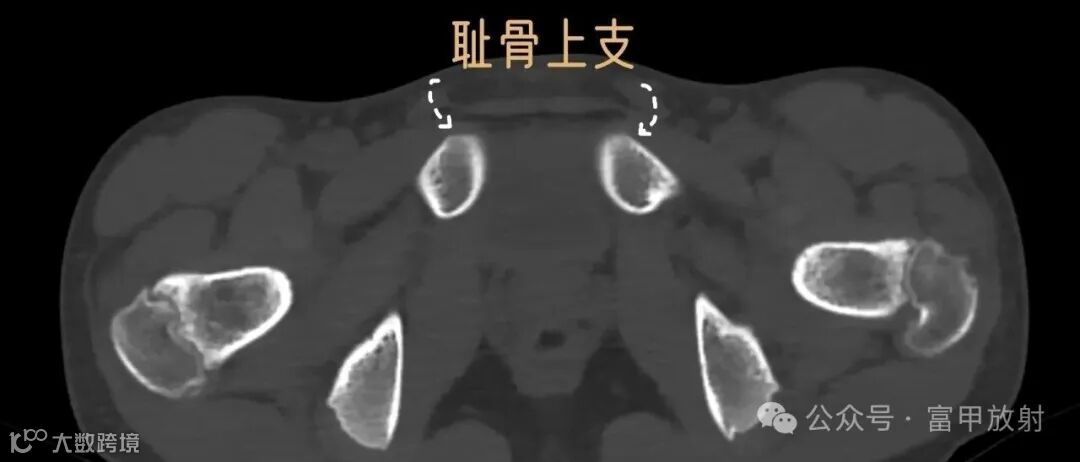

耻骨下支与坐骨分界在哪里?

坐骨结节是坐骨支的突起,是腘绳肌等附着的地方,耻骨结节是耻骨上支内侧缘的突起,腹股沟韧带附着点,在X线上坐骨结节也许估计到,耻骨结节基本上找不到,在这基础上作测量定位置,可靠性会不理想。以下这个简单的方法也许可以帮助到你。